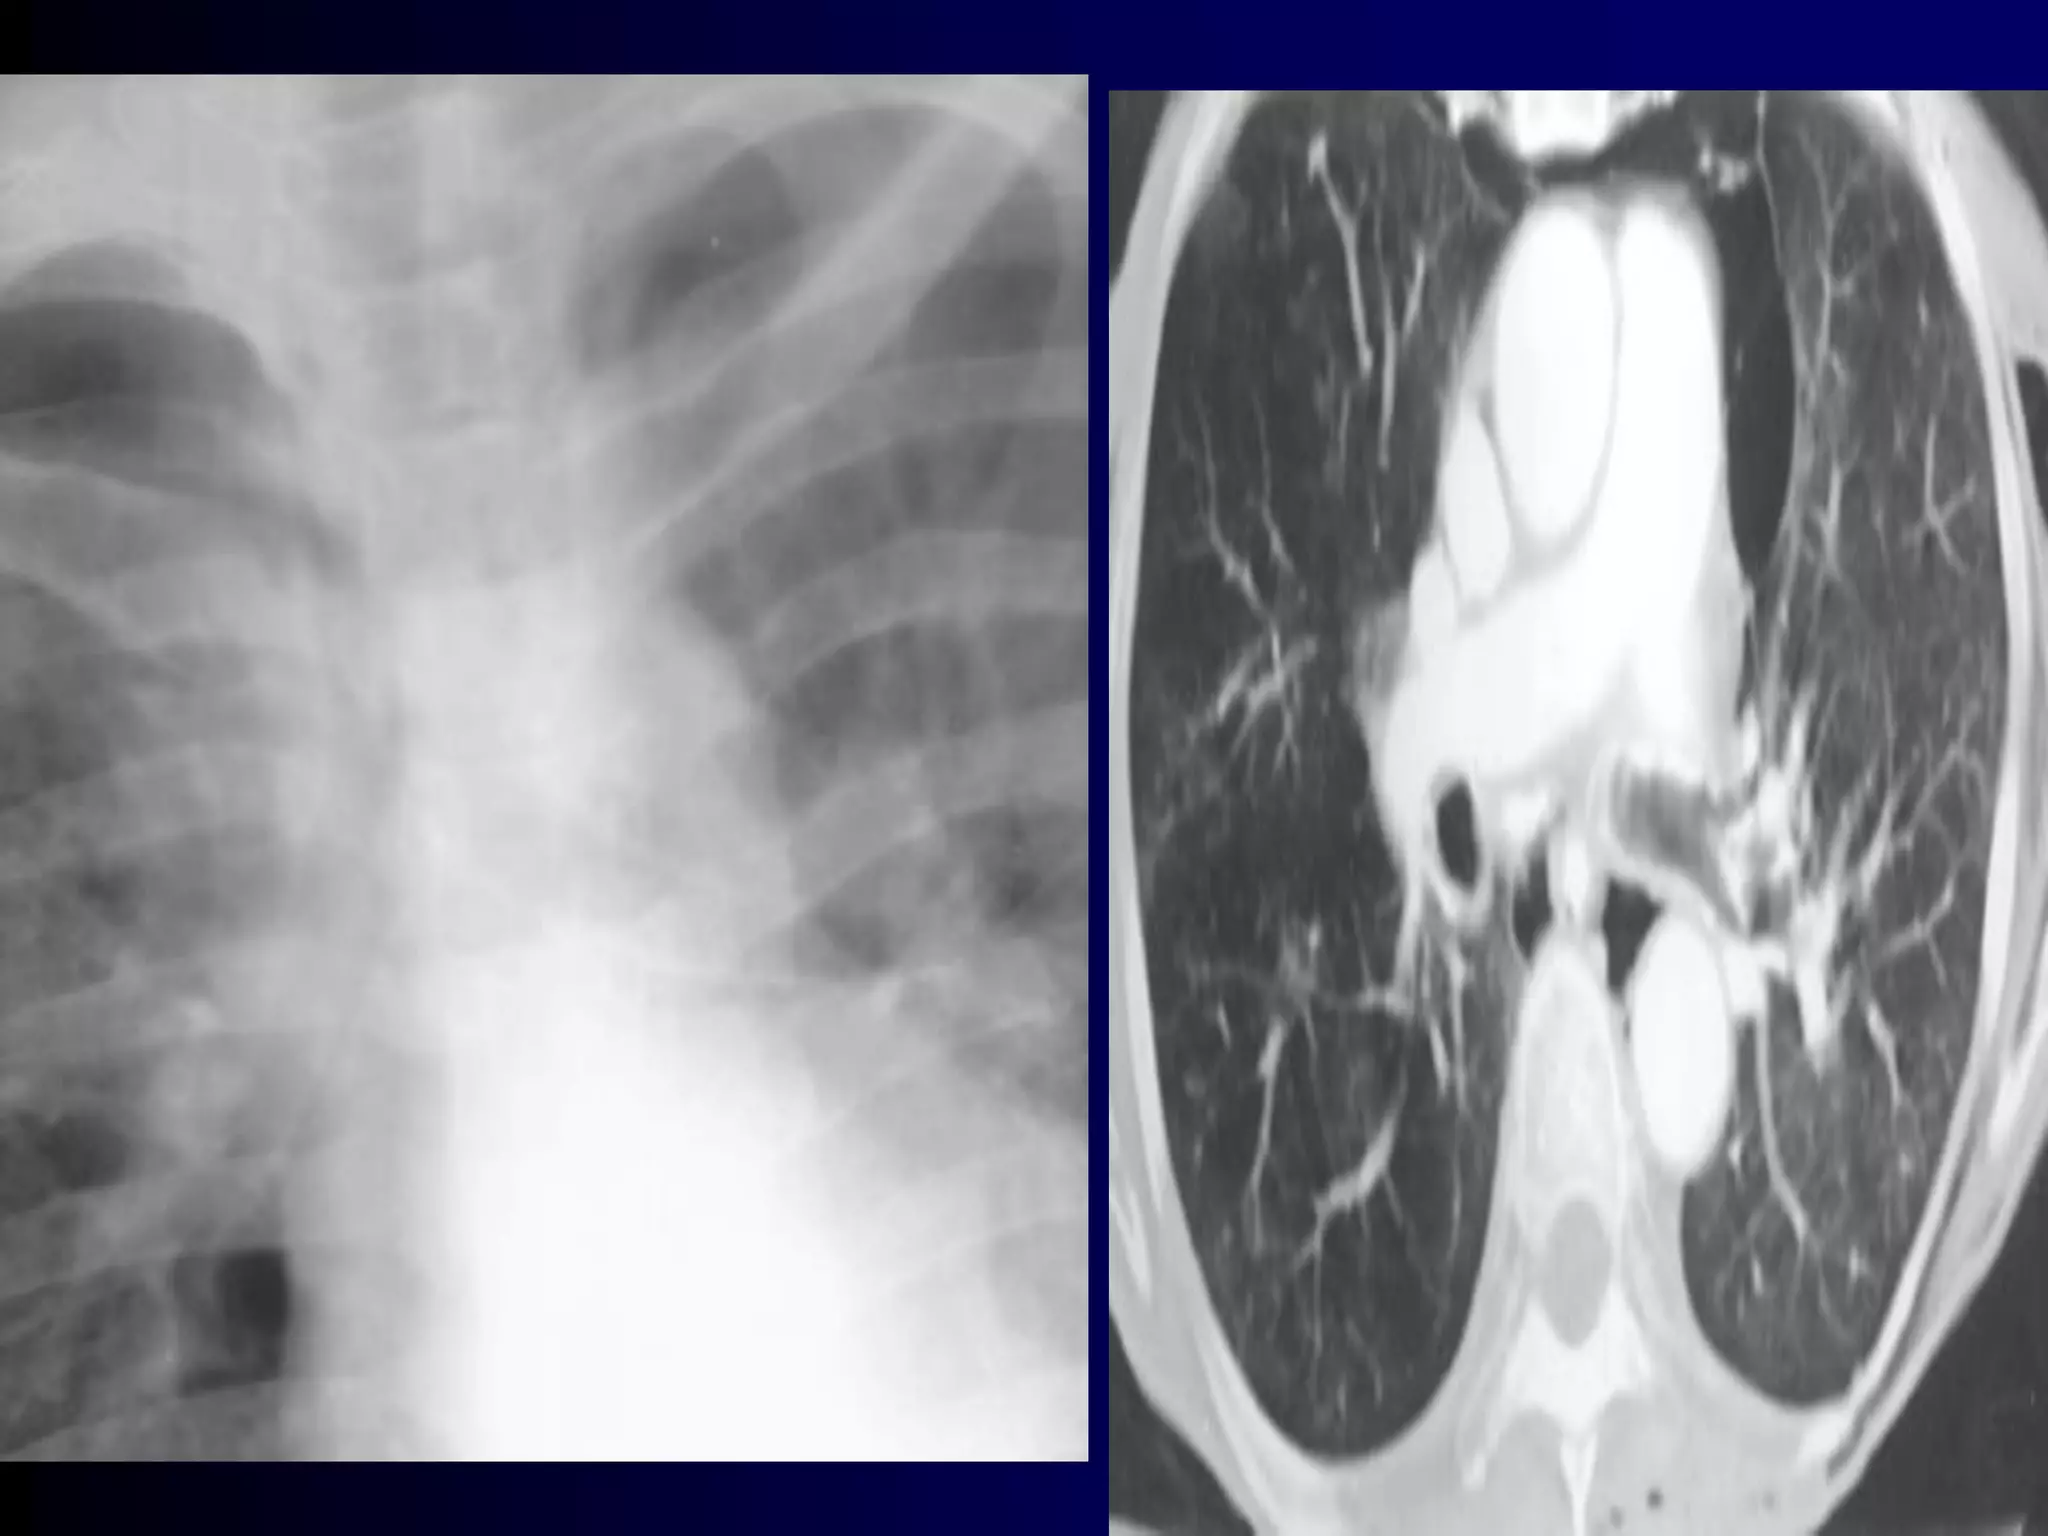

Wheezing in

Children

Bronchiolitis

136

What Is Bronchiolitis?

 Bronchiolitis is acute inflammation

of the airways, characterised by

wheeze

 Bronchiolitis can result from a viral

infection

 Respiratory Syncytial Virus (RSV)

may be responsible for up to 90%

of bronchiolitis cases in young

Chronic Wheezing

 Thriving child – Happy wheezer

 Child failing to thrive - Causes

Exclude other conditions

 Structural problems: bronchoscopy

 Bronchiectasis: HRCT scan, BAL